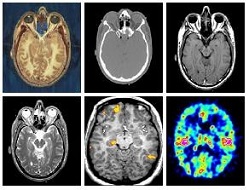

Imagerie biomédicale

Détection de neurone en imagerie à fluorescence par modèle

Intégration d'un système de navigation 3D et d'une source d'image acquise par CT-scan

Mesure de paramètres morphologiques de neurones à partir d'images obtenues par microscopie confocale

Quantification d'expression protéique au sein de cellules soumises à un procédé d'immunofluorescence